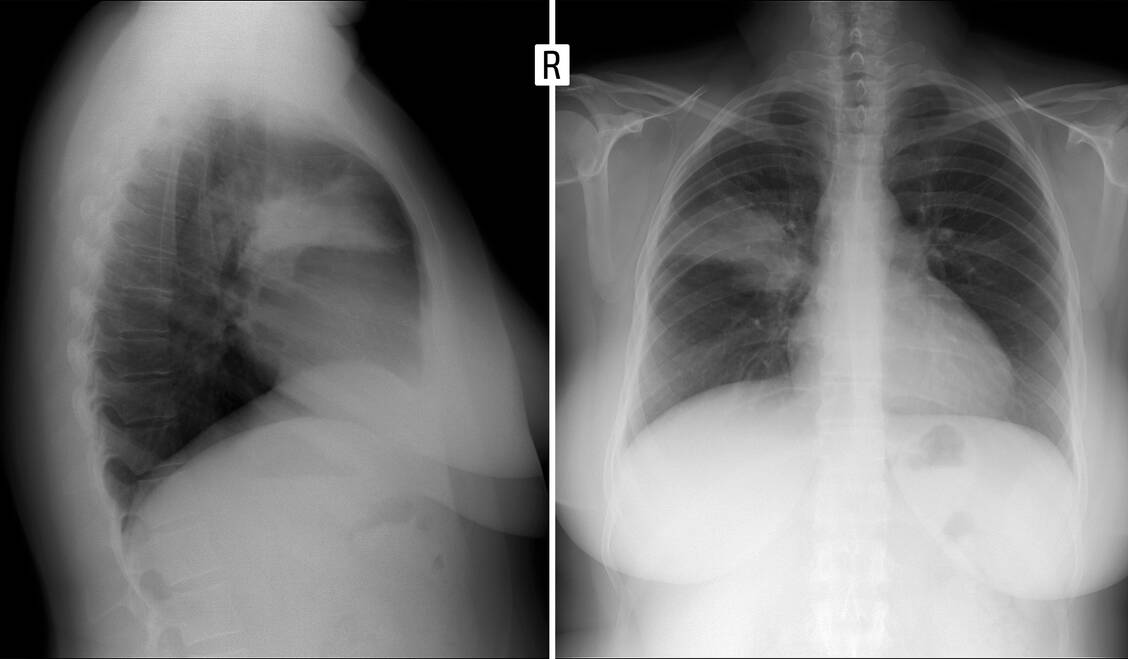

Röntgenaufnahme der Lunge (Ausschnitt in zwei Ebenen): Es ist eine Pneumonie im Lungenoberlappen rechts zu erkennen (Segment 2). / Foto: Shutterstock/Vanzittoo

Zur Unterscheidung einer schweren akuten Bronchitis von einer Pneumonie ist eine Röntgenaufnahme der Lunge (in zwei Ebenen) erforderlich. Nur Spezialisten sehen das pneumonische Infiltrat auch im Ultraschall. Hilfreich kann die Bestimmung des C-reaktiven Proteins (CRP > 20 mg/dl) oder von Procalcitonin (PCT > 0,5 ng/ml) im Serum sein.